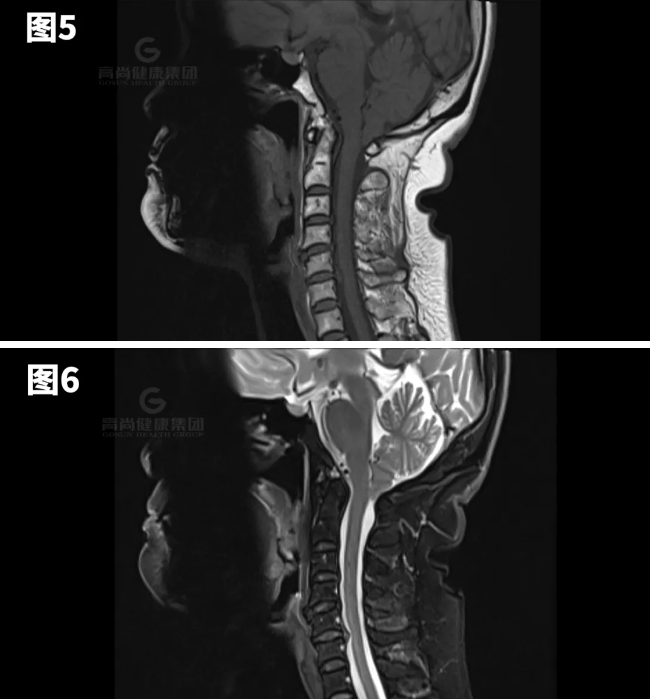

图1-7示小脑扁桃体向下疝出约8mm。

矢状位:扁桃体延伸到枕骨大孔下方,脑干压迫斜坡。

横断位:移位的扁桃体导致周围脑脊液闭塞、髓质前移以及脊髓动脉和椎动脉受压。